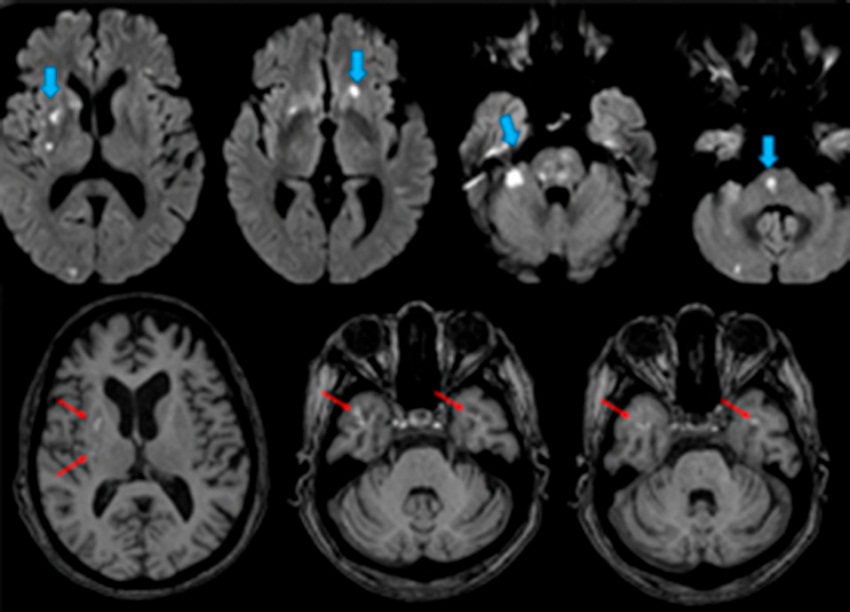

Su evolución fue desfavorable, presentó disnea progresiva y edema agudo de pulmón. En el ecocardiograma Doppler color transtorácico (ETT) se evidenció una imagen móvil en la valva anterior mitral, por lo que se interpretó el cuadro como EI. Se rotó el esquema antibiótico a imipenem y gentamicina, y en la evolución presentó foco neurológico facio-braquiocrural derecho. La resonancia magnética de encéfalo evidenció imágenes focales múltiples en el hemisferio cerebeloso derecho y la sustancia blanca subcortical bihemisférica, compatibles con focos embólicos (Figura 1 A). En la evolución presentó episodios febriles diarios sin nuevo rescate bacteriológico y falla renal aguda no oligúrica, sin requerimiento de diálisis. Fue derivada a nuestro centro para resolución quirúrgica de su EI complicada resistente al tratamiento médico. Ingresó afebril, sin signos de insuficiencia cardíaca, vigil, orientada en espacio y persona, desorientada en tiempo.

Se realizó nueva resonancia magnética de encéfalo donde se observaron imágenes hiperintensas en T1 en putámen y globo pálido derechos y el lóbulo temporal bilateral compatibles con sangrado subagudo. (Figura 1 B)